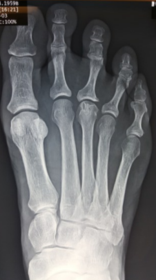

Describe the alignment of metatarsal 2 | There is no angulation nor displacement of the distal segment relative to the proximal segment. |

Describe the alignment of metatarsal 3 | The distal segment is displaced laterally (50% apposition) and angulated medially. |

Describe the alignment of metatarsal 4 | The distal segment is displaced laterally (75% apposition) but there is no apparent angulation. |

Describe the tubulation of the metatarsals | Metatarsals are overtubulated - decreased girth. |